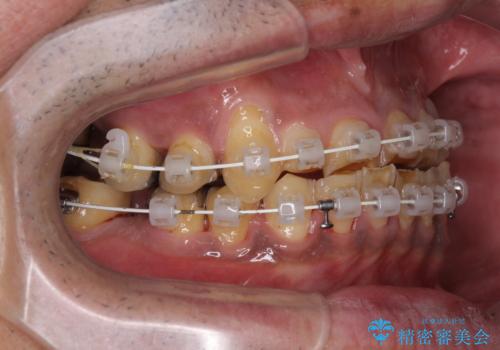

- 矯正装置

- 審美装置

奥歯の欠損が散見されており、銀歯の装着されている歯も多いため、ワイヤー矯正にて歯列を調整し、その後オールセラミッククラウンにて補綴治療を行うこととしました。

矯正治療は想定通り長期化しましたが、しっかりと奥歯の咬み合わせを向上させて前歯の被蓋を改善させることができました。